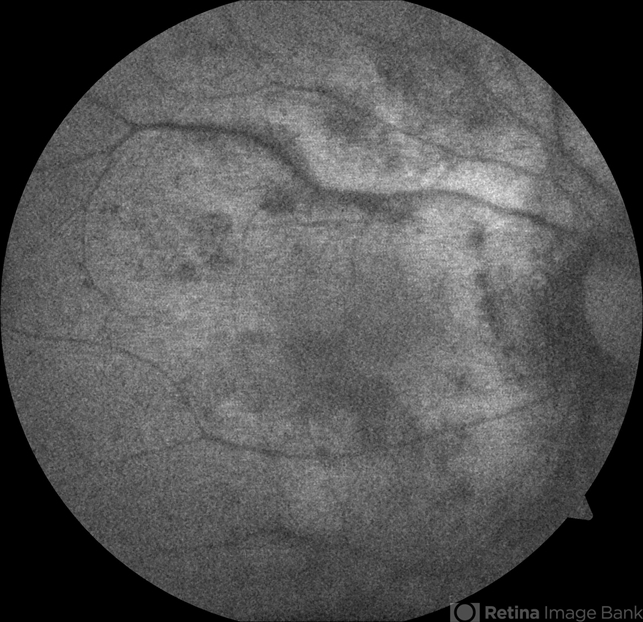

- birdshot chorioretinopathy, birdshot retinochoroidopathy

- Moises Castro, Instituto de Ojos y Piel, Carolina, PR

Zeiss, Visucam NM/FA - Description

- 64-year-old Puerto Rican woman consulted due to the presence of 1+ vitreous cells. The fundus examination revealed orange to yellow lesions dispersing from the disk. Work-up revealed she was HLA-A29 positive and the suspected diagnosis of Birdshot Chorioretinopathy was made. Chest X-Ray, FTA-Abs and RPR were negative.